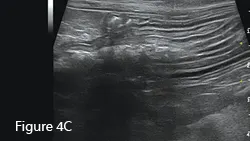

Sagittal ultrasound image of a canine duodenum (between arrows). The small intestine is usually empty or contains minimal fluid and/or gas (*). Bowel-wall layers are readily identified with the hypoechoic mucosal layer (M) being thickest, surrounded by thin submucosal (hyperechoic), muscularis (hypoechoic), and serosal (hyperechoic) layers. Transverse images of small intestine are present in the near field.